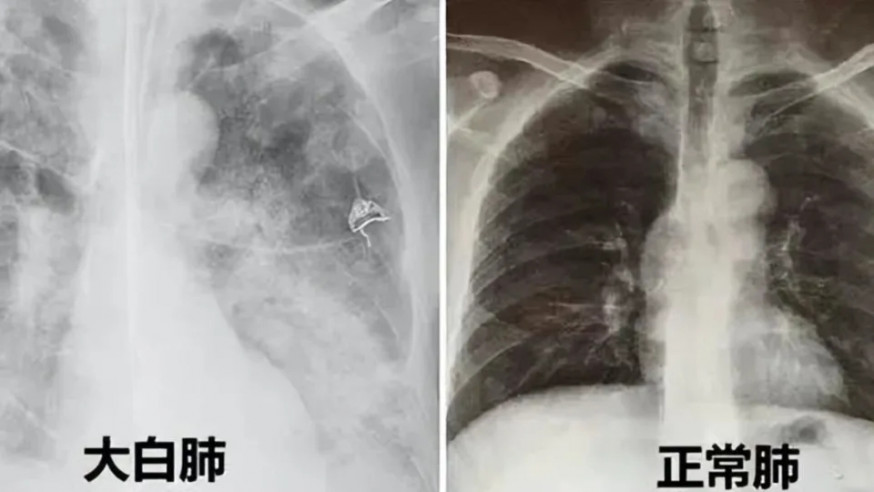

內地確診者再現「白肺」

內地近日疫情升溫,更有指部分地區單日確診個案多達數以十萬計。內媒報道,近日網上有流傳指Delta與Omicorn變種病毒再次於內地肆虐,並指確診者的肺部CT掃描(電腦斷層)結果顯示出現「白肺」,疑與原始病毒株的出現及接種疫苗有關。

國家衛健委醫政司司長焦雅輝亦有針對有關傳聞回應,解釋「白肺」的說法只是肺部影像學表示的一個口語化描述,而非肺部組織變了白色。她稱,不只是感染新冠病毒會令CT結果出現「白肺」,感染其他呼吸道合胞病毒或流感病毒亦會導致相關現象。

她續稱,出現「白肺」代表了肺泡內有炎症,令肺部被滲出的液體或炎性細胞填滿,導致CT檢查中的光線無法穿透肺部出現白肺,與新冠肺炎病毒並沒有直接關係。

「白肺」在臨床上十分罕見

焦雅輝再補充,現時網上流傳的「白肺」並非真正的白肺,白肺只適用於形容較嚴重的患者,在肺部CT,白色影像面積達70-80%才可稱之為「白肺」,而且就臨床角度而言此現象十分罕見。高齡為出現「白肺」的一大因素,然而若再有長期病患或重病患者則需要多加留意。若老人出現呼吸困難等情況時務必要到急症室求診。